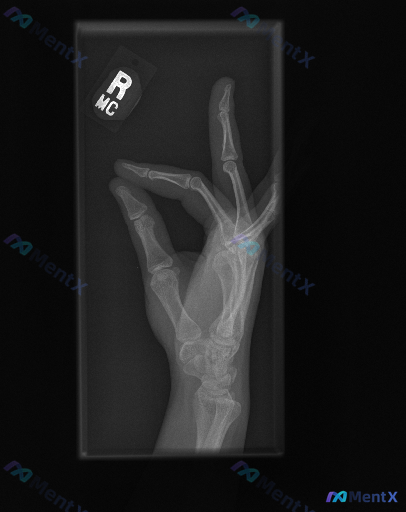

整理到一份右手侧位X光片的影像资料,结合报告看属于典型的骨科急症,但先只看描述,大家第一眼思路会落在哪里? 先给基础影像表现: - 成年患者(骨骺已闭合) - 拇指近节指骨基底部骨皮质不连续,可见透亮骨折线,累及关节面,伴移位 - 其余掌骨、指骨、腕骨未见明确骨折征象 - 拇指掌指关节周围软组织密度...